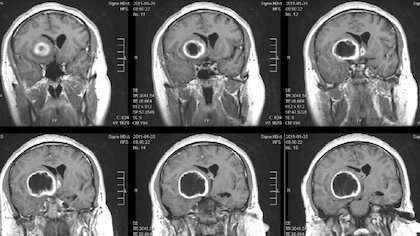

Immagine: Brain tumor. Credit: UTW.